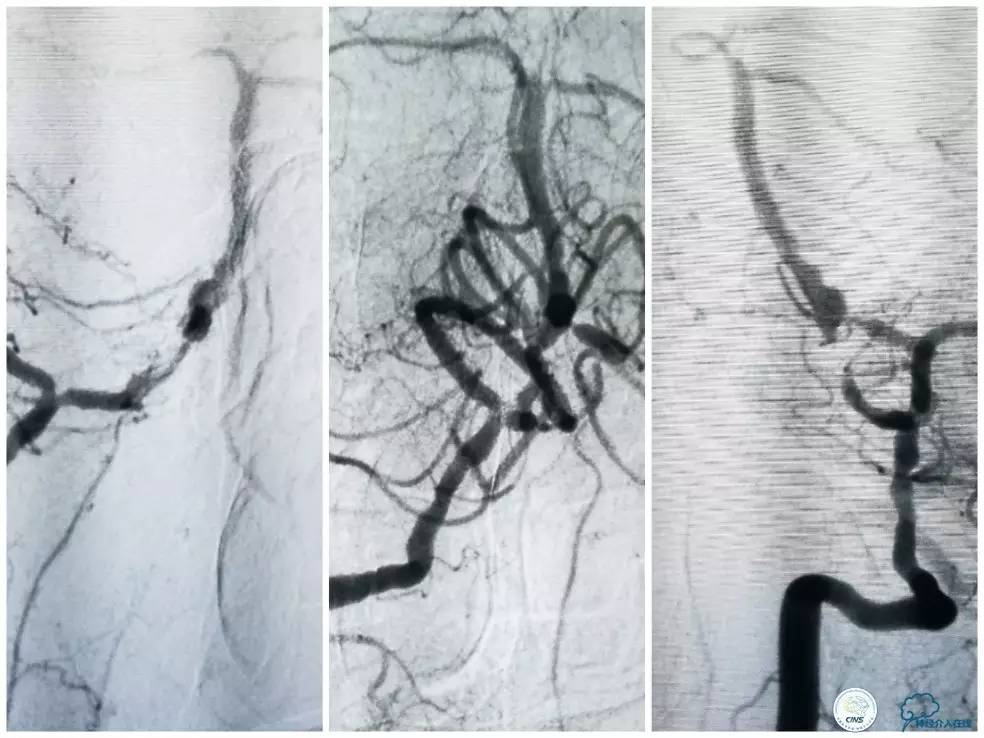

术前DSA:右椎动脉V1段长段重度狭窄,V4-基底动脉交界区显影浅淡,狭窄程度重,但具体程度显示欠佳(图7)。左椎动脉V1段闭塞,左椎动脉V2远段经侧支代偿显影,V3段以远未见显影(图8)。前循环造影未见明显前循环向后循环代偿(图9)。

图7

图8

图9